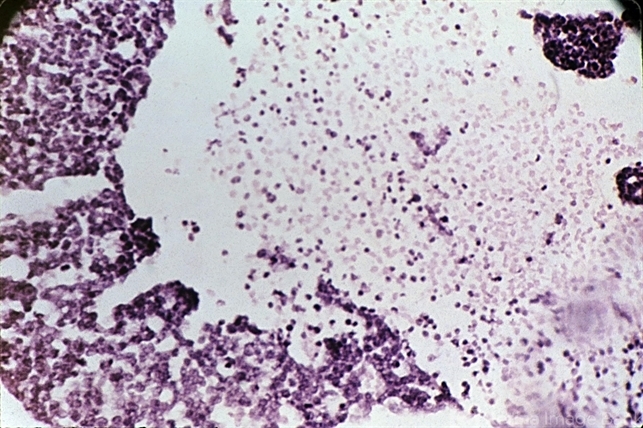

- retinoblastoma, retinal necrosis

- High-power view of a retinoblastoma undergoing necrosis.